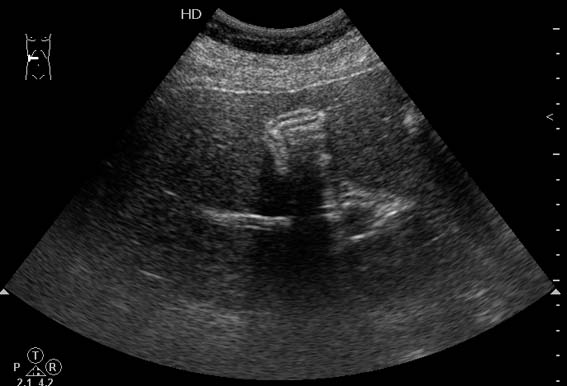

Молодой мужчина с болями в эпигастральной области.

Осматривался дважды натощак. Выявлены изменения желчного пузыря.

Печень, селезенка при УЗИ не изменены.

Думаю,что это не просто пустой ж.пузырь,он содержит гиперэхогенное включение в середине,повторяющее форму ж.пузыря и дающее позадиакустическую тень.Возможна кальцифицированная аскарида :)

Нефункционирующий желчный пузырь содержит гиперэхогенное включение.

Первый ж.пузырь удален, клинический диагноз "сморщенный желчный пузырь, ЖКБ", гистология - фиброз стенок желчного пузыря.